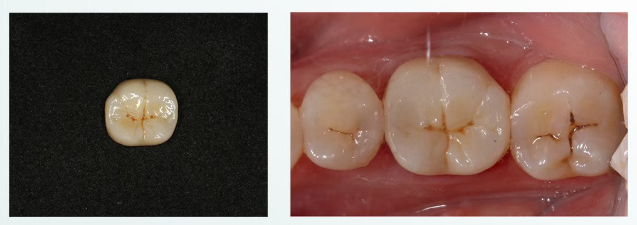

第五次就诊

去除暂冠,清洁基牙,隔湿,玻璃离子粘接。